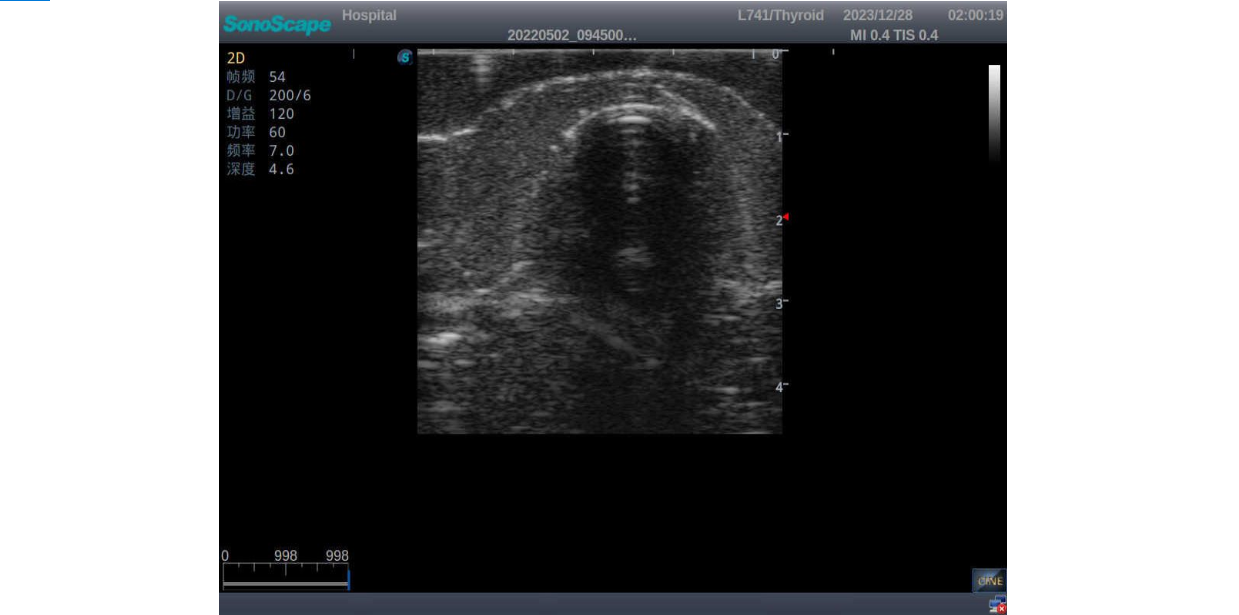

Thyroid Ultrasound Training Model

This product has true-to-life male torso including head, neck, shoulder and upper chest. It serves as an excellent teaching tool for identification of various types of normal thyroid, thyroid adenoma, thyroid cancer, nodular goiter, thyroid cyst and training on proper thyroid scanning techniques.

2)       Ultrasonically realistic materials at neck & various types of real ultrasonic machines in clinical available, developing realistic imaging like common carotid artery, internal jugular vein, trachea, thyroid cartilage, cricoid cartilage, lobes of thyroid gland and isthmus

3)       It comes with four (4) thyroid modules and can show five (5) ultrasonic images: normal thyroid, thyroid adenoma, thyroid cancer, nodular goiter, thyroid cyst

Thyroid cancer with irregular mass, unclear border, uneven internal echo or calcification strong echoes